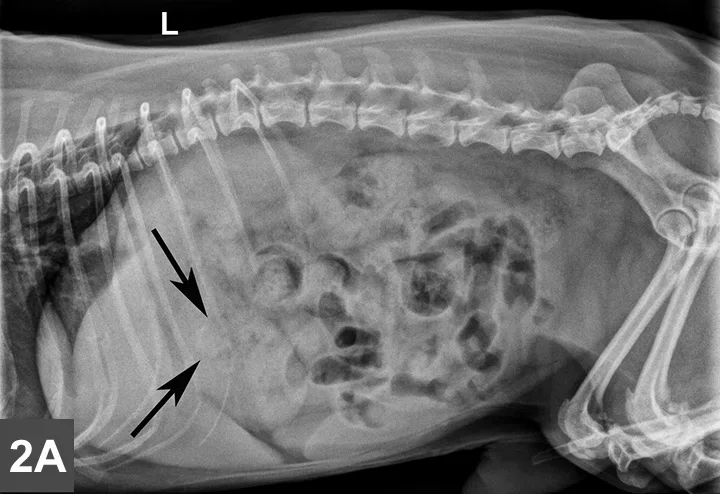

Left lateral (Figure 1A) and VD (Figure 1B) radiographs of the abdomen were obtained. Although thoracic radiographs were also taken, the findings were considered normal and, therefore, are not included here.

Figure 1A & B

Left lateral (Figure 1A) and VD (Figure 1B) views of the abdomen.

Radiographic Findings

A mottled mineral opacity measuring ~12 mm in diameter is seen just caudal to the last right rib in the VD view, near the pyloroduodenal junction (Figure 2B, black arrows), and superimposed over the pylorus in the lateral view (Figure 2A, black arrows). This opacity could be a foreign body or a mineralized mass or lymph node. Heterogeneous soft tissue material, compatible with ingesta, is present in the gastric lumen as well as throughout the intestines, but no abnormal distention is evident. The liver extends past the costal arch with mild caudal displacement of the gastric axis, consistent with mild hepatomegaly; the margins are smooth. The remaining viscera and serosal detail are normal.

Figure 2A & B

Same lateral and VD radiographs as in Figure 1A and B showing mineral density just caudal to the last right rib in the VD view (Figure 2B, black arrows) near the pyloroduodenal junction and in the lateral view (Figure 2A, black arrows) superimposed over the pylorus.